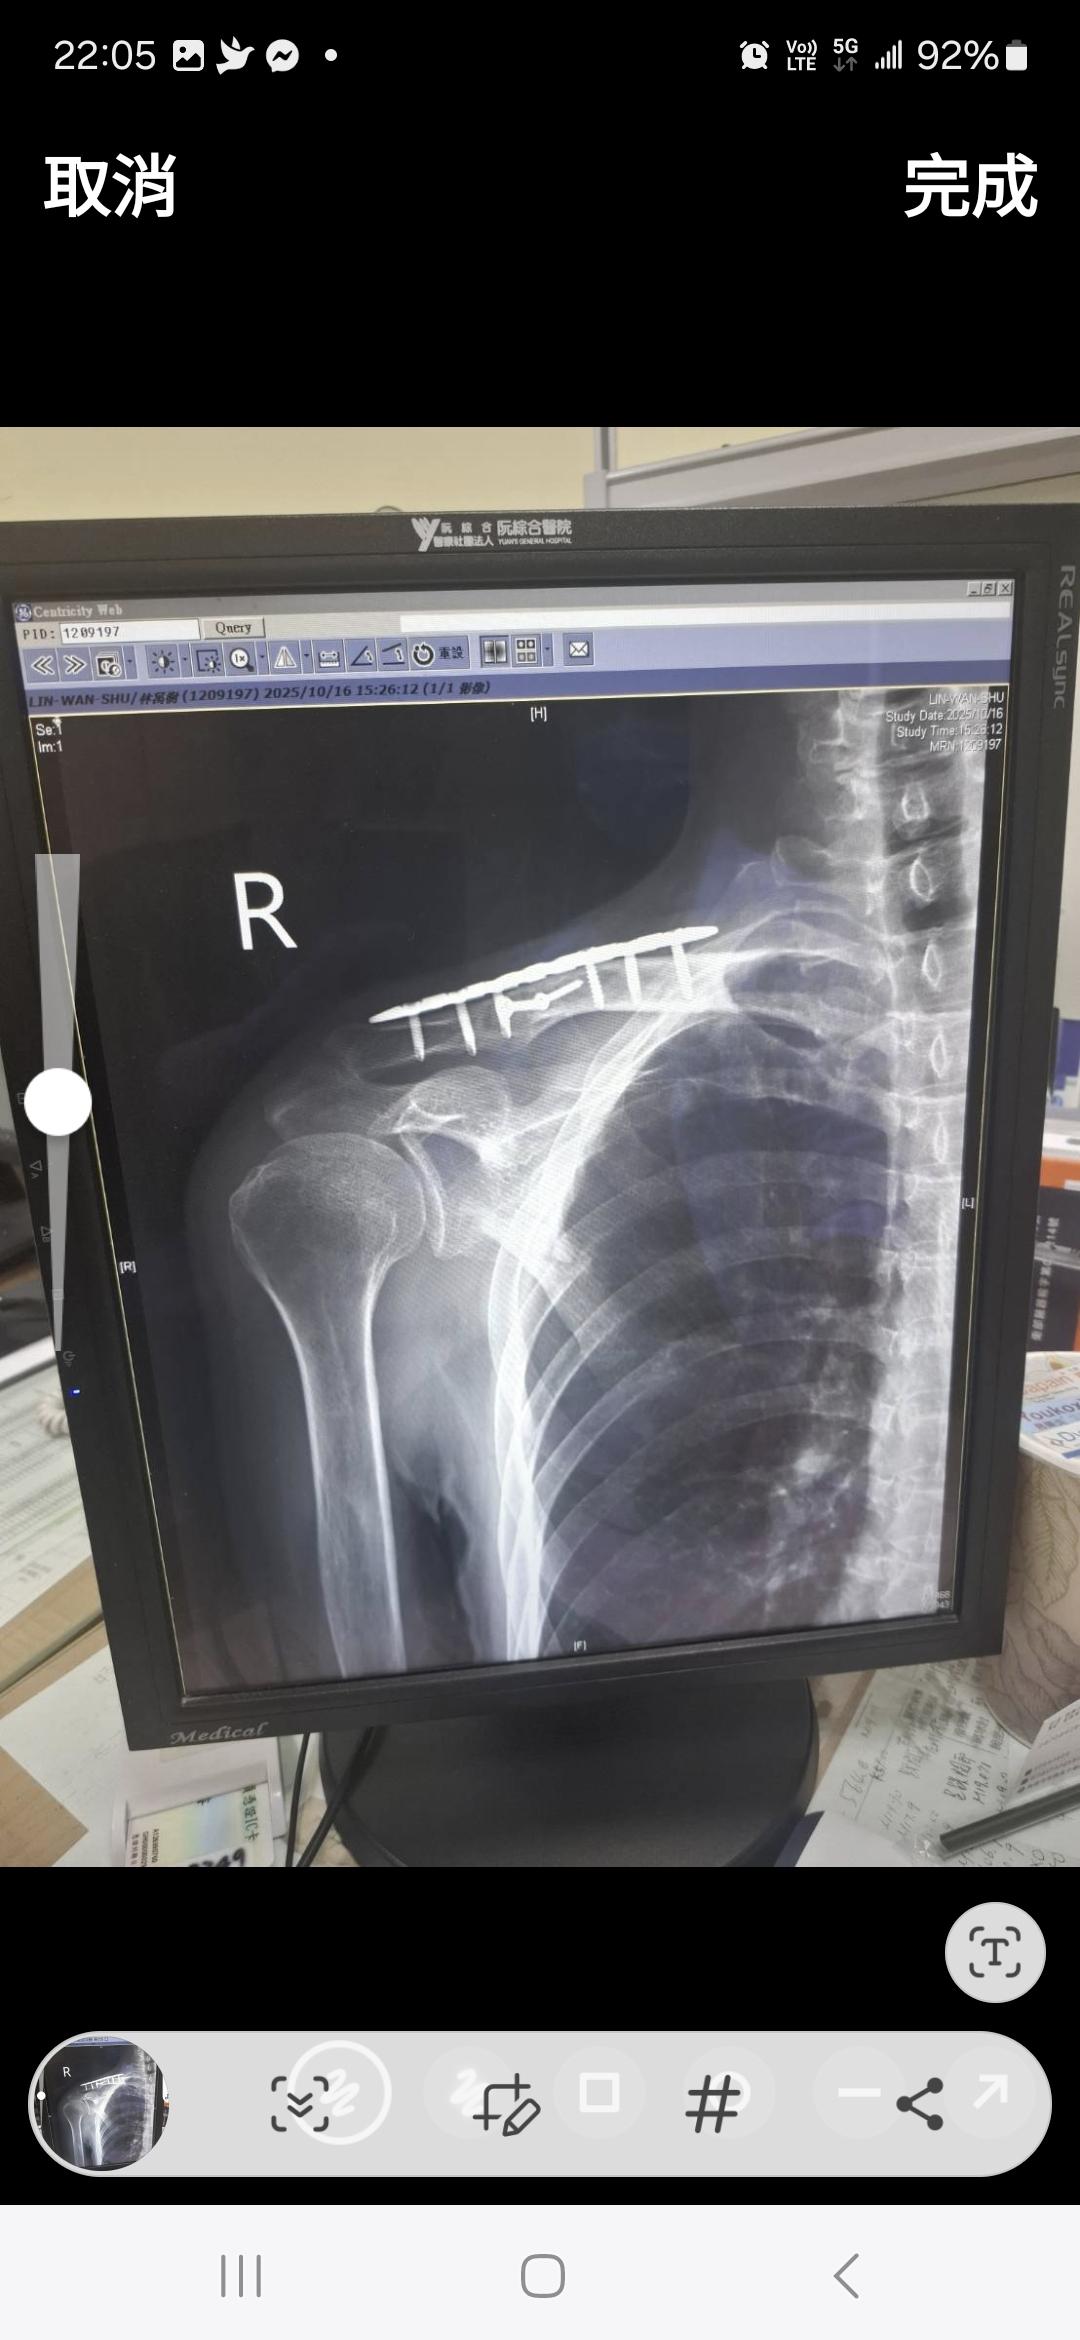

這張是上個月照的

骨架固定著?

這樣自費約63000